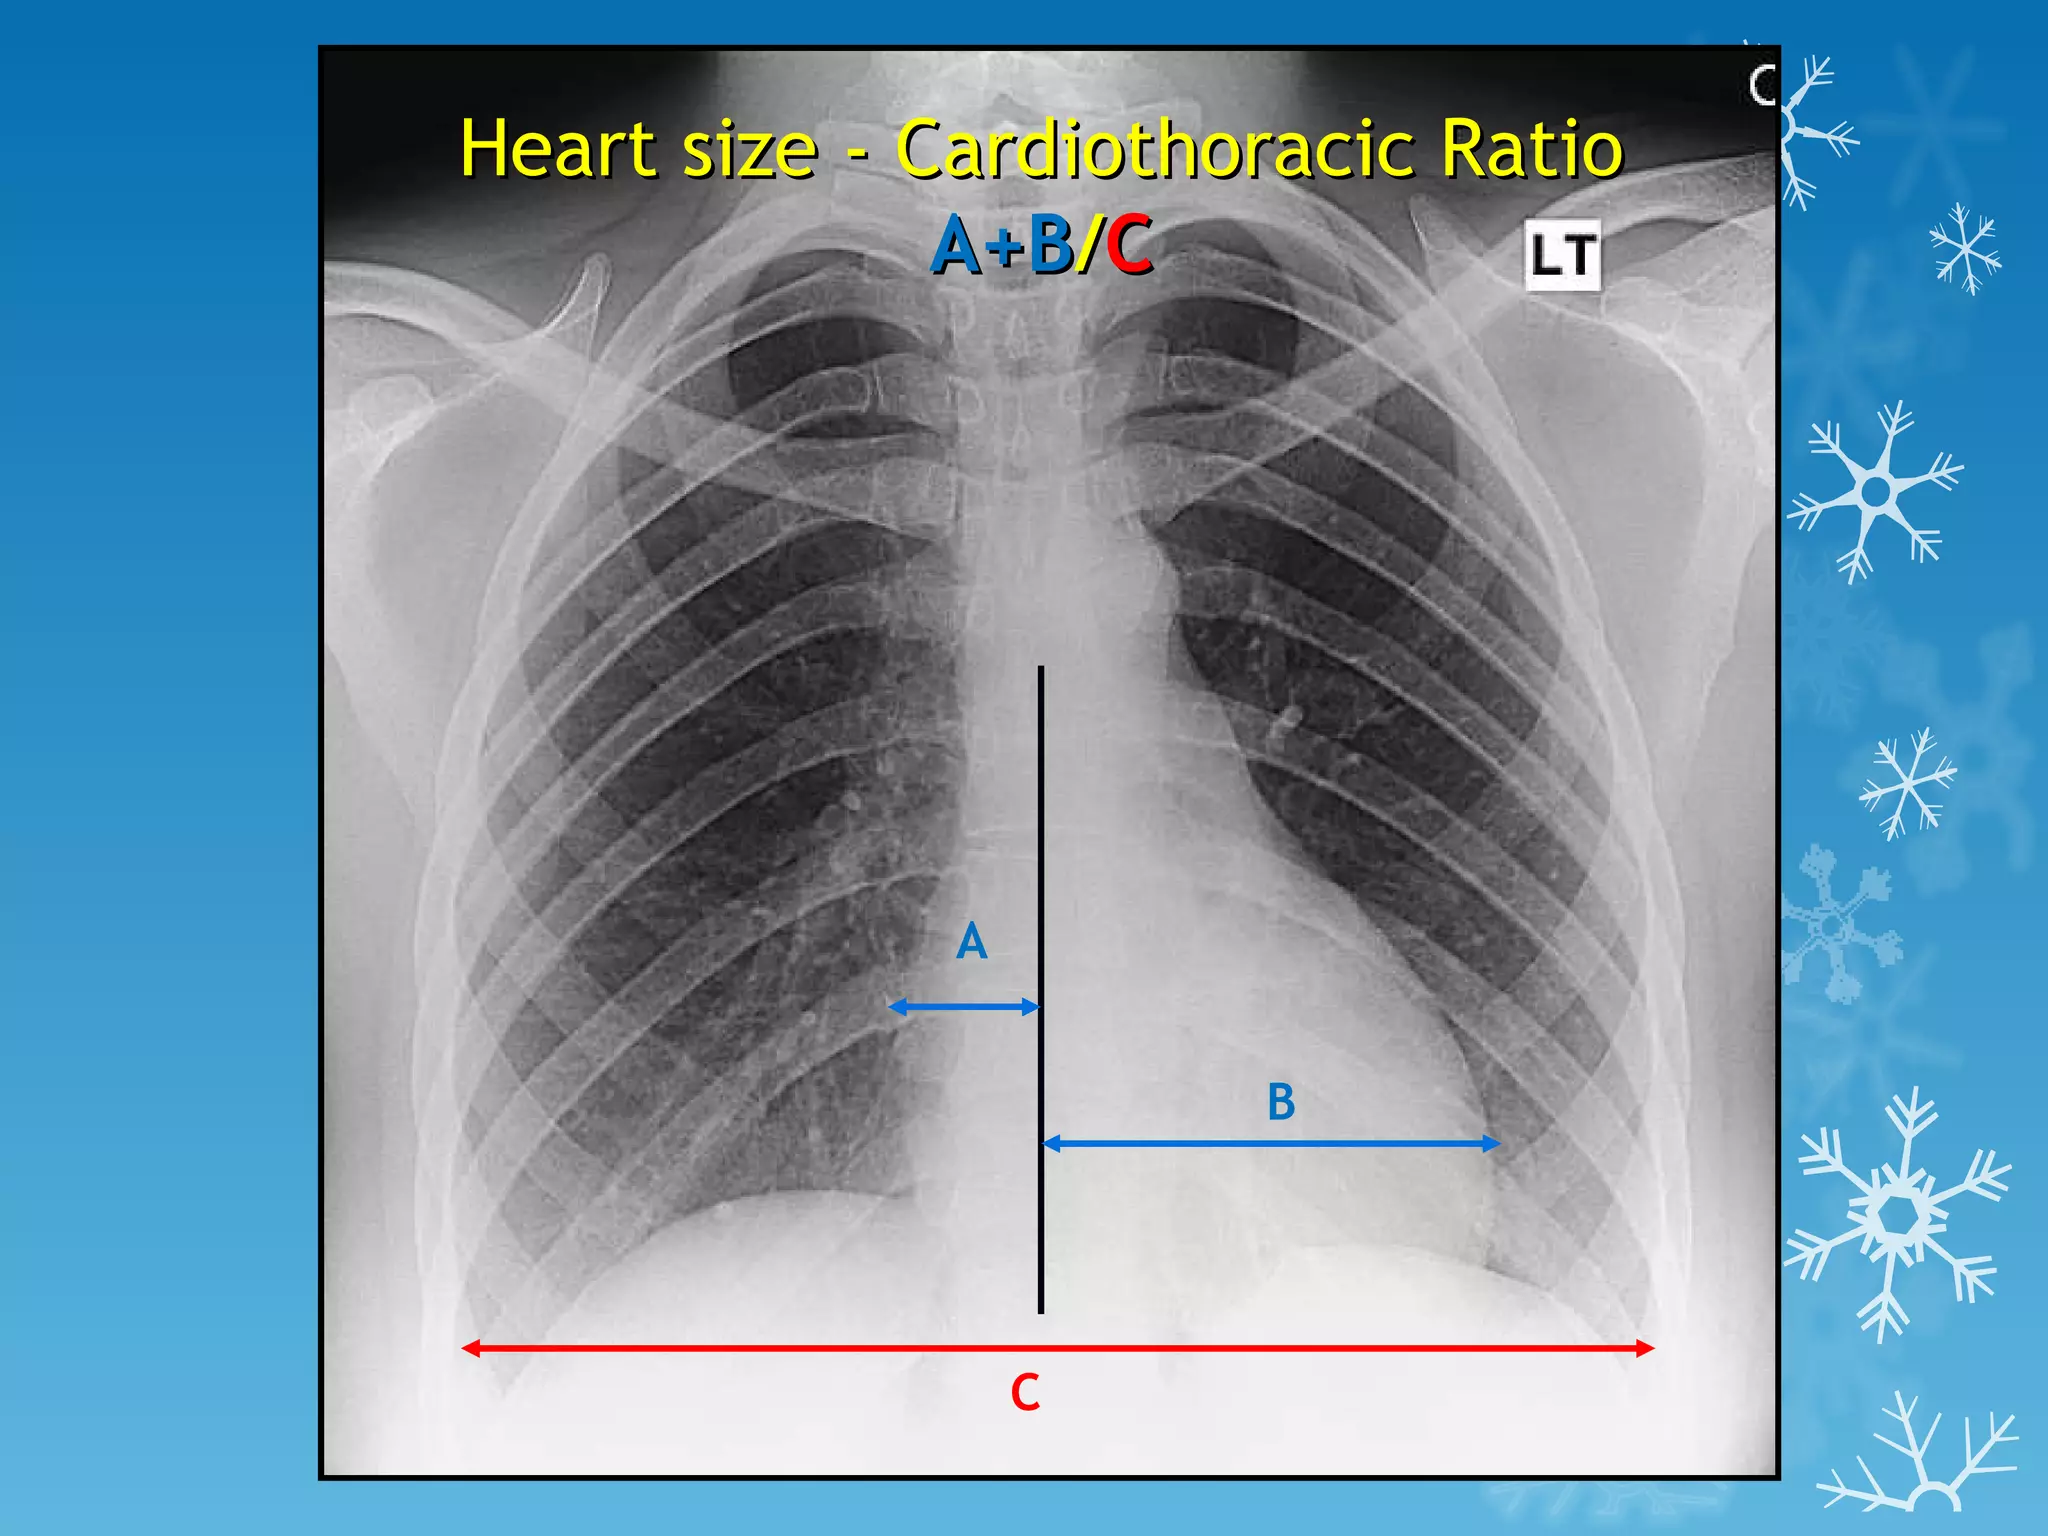

This document discusses chest x-ray interpretation and provides guidance on evaluating x-rays. It explains that tissue density determines how an x-ray beam penetrates, with denser tissues appearing whiter and less dense tissues appearing blacker. It also outlines different chest x-ray views and factors to consider like patient orientation, age, gender, and rotation. Abnormalities are described as appearing too white, too black, too large, or in the wrong place. The document stresses a systematic approach of identifying, localizing, describing lesions, and providing differential diagnoses.